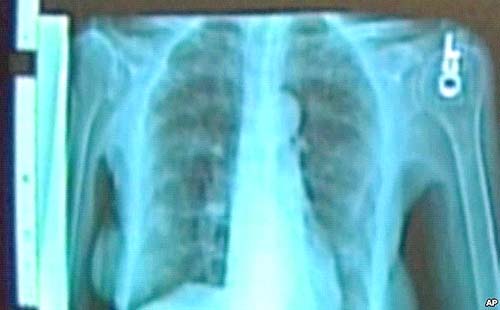

Các nhà khoa học phát hiện ra Ung thư phổi có thể nằm ẩn dấu trong vòng 20 năm

Ngày 9/10/2014.- Các nhà khoa họcphát hiện ra Ung thư phổi có thể nằm ẩndấu trong vòng 20 năm (Scientists Find Lung Cancer Can Lie Hidden for 20 Years). Vào hôm thứ năm các nhà khoa học cho biết ung thư phổi có thể nằm im hơn 20 năm trước khi quay sang gây chết người, giúp giải thích tại sao một căn bệnh giết chết hơn 1,5 triệu người một năm trên toàn thế giới là rất dai dẳng và khó điều trị.

Ung thư phổi